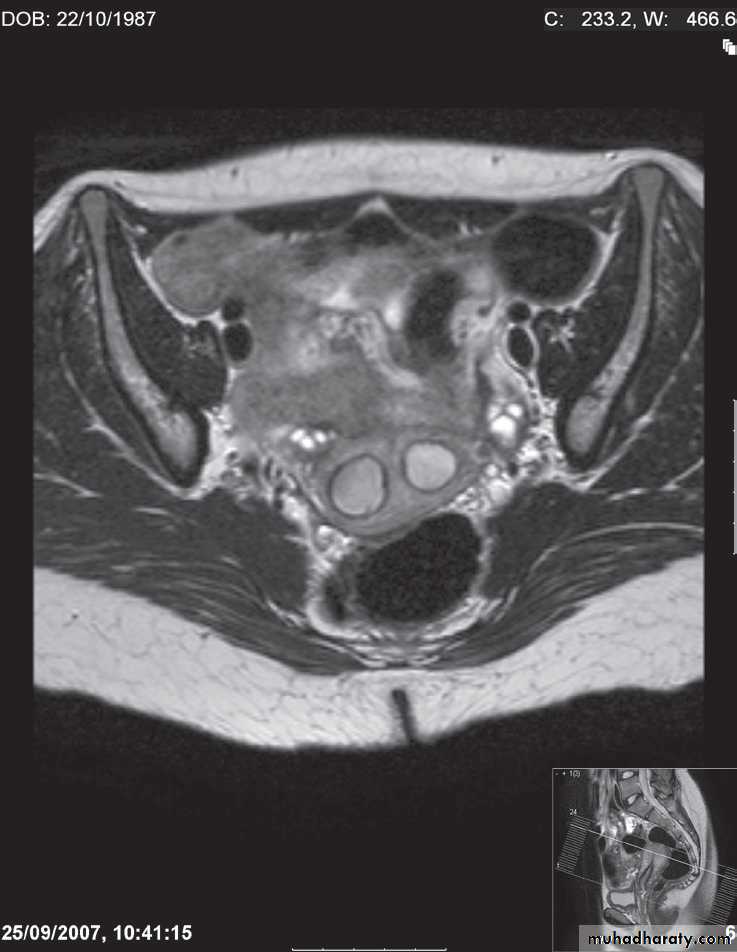

Magnetic resonance imagingPelvic anatomy is very well demonstrated because of the excellent soft tissue contrast afforded by MRI. Images are usually taken in the axial, coronal and sagittal planes . T2-weighted sagittal images show the vagina and cervix in continuity with the body of the uterus.

The zonal anatomy of the uterus is best demonstrated on T2-weighted images, with the endometrium having a high signal intensity, the adjacent inner myometrium (junctional zone) a low signal intensity, and the myometrium an intermediate signal intensity .

The cervix may be predominantly low in signal intensity.

Variations of uterine anatomy are well delineated on MRI-The ovaries are of intermediate signal intensity and often contain multiple high signal follicles on T2-weighted images

-The broad ligaments can also be identified in MRI